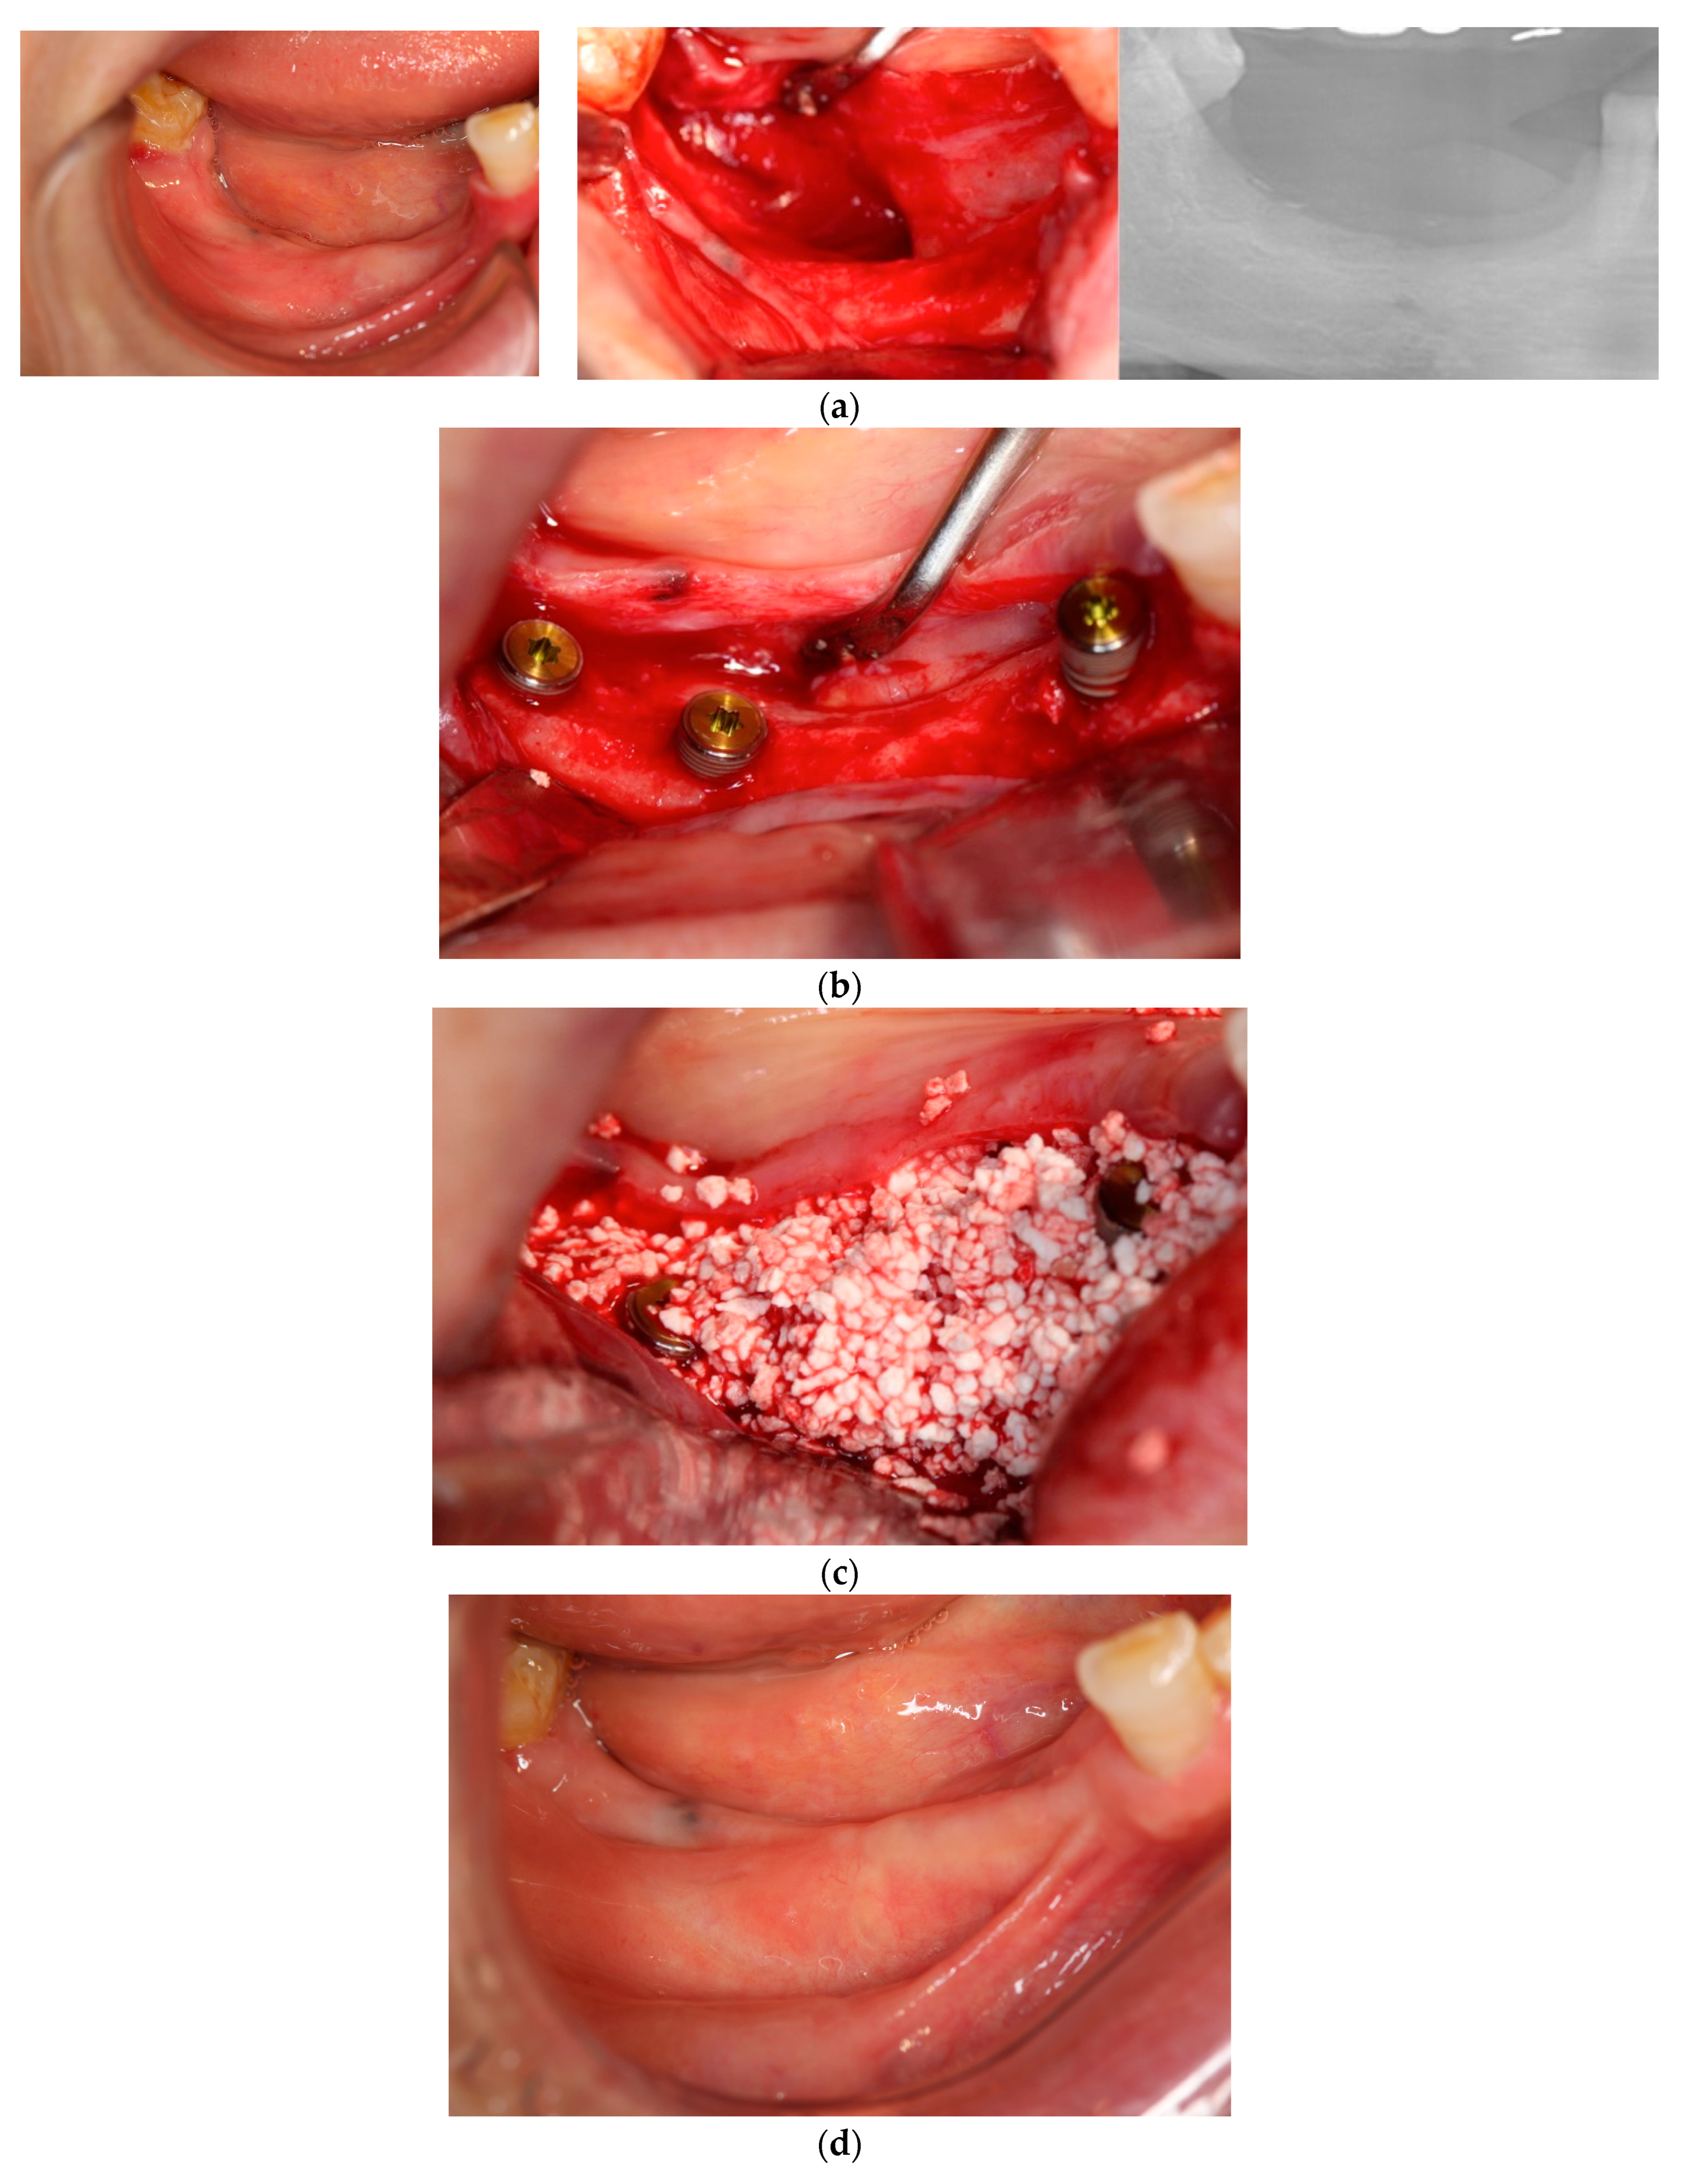

Figure 3. Case 4: Simultaneous approach of implant placement and vertical ridge augmentation using carbonated apatite (CA; no membrane). (a) Preoperative view. A vertical bone deficiency was observed at the mandibular right molar area on the panoramic radiograph. Soft tissue loss was also observed. (b) Implant placement. Implants were placed at the 44, 46, and 47 sites. Each implant achieved primary stability of over 30 N·cm. (c) CA graft. After a releasing incision to the lingual and buccal sites, CA was placed in the bone defect area to the platform level. (d) Immediately after treatment. Sutures were performed closely with interrupted sutures. (e) Five months after, before uncovering. Any complications were not observed. (f) Upon uncovering. Vertical and horizontal bone regeneration was observed at the mandible right molar area. The 44-implant thread was slightly exposed. (g) Twelve months after implant placement. Regenerated bone was maintained on a panoramic radiograph and no inflammation was observed in the peri-implant soft tissue.

In each case, all implants ensured osseointegration during uncovering, and the peri-implant hard tissue was deemed stable. The results for Cases 2 and 4 are shown in Figure 2 and Figure 3, respectively. For SiRP, after 5 months of RP treatment, the implant was placed in the regenerated bone up to the height of the preserved alveolar ridge (Figure 2). In Case 4, the bone was hard and only 7 mm remained from the alveolar ridge to the inferior alveolar canal. The minimum length of the implant in this case was 8 mm, and to avoid postoperative complications such as paralysis, a safety margin of 2 mm was established, and the implant was placed after drilling for 5 mm. In addition, the molar area had significant vertical bone resorption and narrowing of the oral vestibule, and it was predicted that brushing would be difficult after the prosthesis. Therefore, the plan was to perform a vertical alveolar crest augmentation. Approximately 4.0 mm of vertical bone regeneration was achieved at implant 46 at 4 months following RA. Additionally, the exposed implant threads appeared to be completely covered with regenerated bone in the panoramic radiograph taken 24 months after prosthetic delivery (Figure 3).